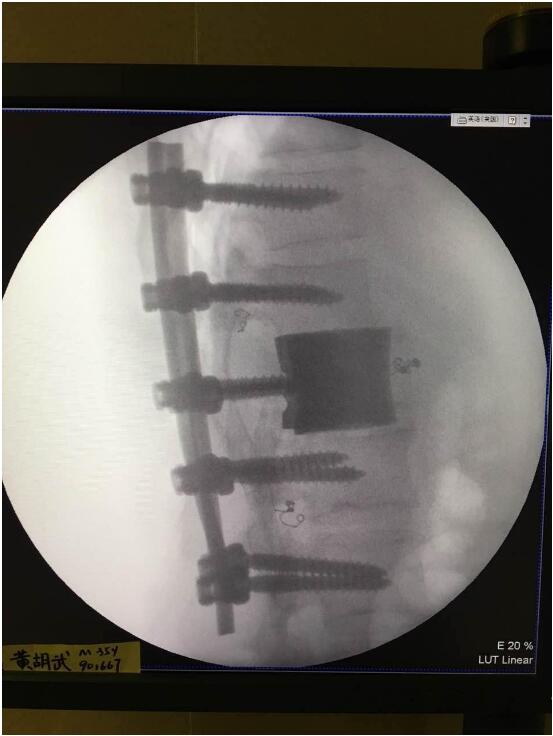

这次手术是广州华钛三维骨科研究中心(华钛三维骨科研究院)与南方医院联合澳大利亚技术科学与工程院吴鑫华院士领导的莫纳什大学增材制造研究中心合作的世界第一例3D打印个性化人工椎体/腰间盘一体化植入手术。南方医院脊椎及骨病外科郑明辉副主任医师在岭南名医陈建庭主任和朱青安教授指导下,与华钛三维工程师陆国赞合作构思设计,澳大利亚莫纳什大学增材制造研究中心主任吴鑫华院士团队进行了一个多月的个性化钛合金3D打印工艺研究,成功打印出符合病人要求的人工椎体/腰间盘一体化植入物。这次手术的成功,标志着中国的3D打印植入物技术在骨科医疗领域达到世界先进水平。

为了更好的完成手术,陈建庭主任、郑明辉副主任医师等骨科专家与华钛三维的3D打印专家从2017年10月份开始筹备该手术。考虑到每一个病人的脊椎形状都存在差异,骨科专家认为用一个现成的标准植入物不大可能匹配病人的生理参数。医学专家和3D打印专家根据病人脊柱的CT扫描数据,为病人的脊柱建立了精准的3D图像。根据这个图像,治疗团队就能够设计并定制出属于病人的个性化植入物。为了使个性化定制的人工椎体与病人椎体之间更好的融合,手术实施前治疗团队先后设计了100多个方案,制作了数十个植入物的术前模型进行研讨。事实证明,手术最终使用的植入物是最适合手术和病人身体情况的。

利用3D打印技术生产出来的人工椎体是完全按照患者的解剖结构完成脊椎结构重建及固定的, 装上一枚精准的、个性化的人工脊椎,患者康复后完全可以正常地生活和工作。过去这种手术常常是使用钛网内填入自体或异体碎骨作为椎体间支撑材料,但钛网一旦移位压迫脊髓,患者就会有瘫痪的风险。这次手术中的脊椎植入物内部具有经过力学优化设计的晶格结构,比传统钛网具有更强的承重力,金属3D打印可以直接制造出这样的复杂结构。

最终在经历近八个小时后,病人的家属终于等到了好消息:人工椎体/椎间盘一体化金属植入物成功植入,手术顺利。由于病人术中出血量小,生命体征平稳,他不用进入ICU观察,直接回到了普通病房。“现在我们都很高兴,成功做出了世界首例人工椎体/椎间盘一体化金属植入物,病人今后可以与常人一样工作和生活。”郑明辉医生说。